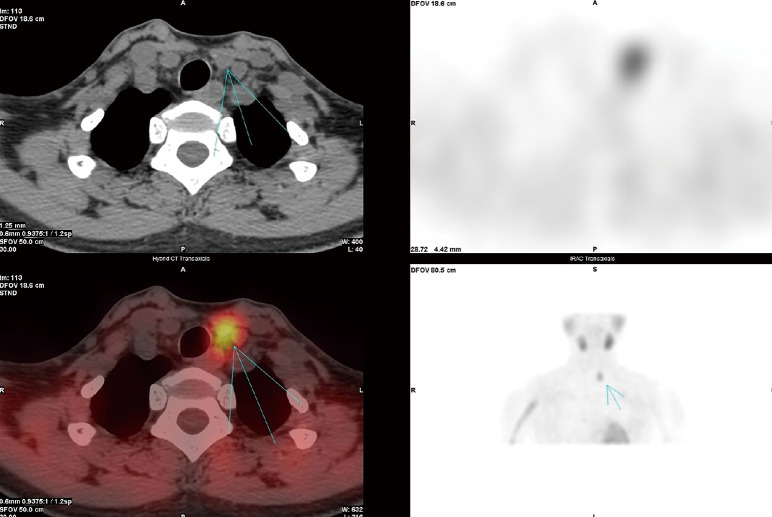

Abstract Image